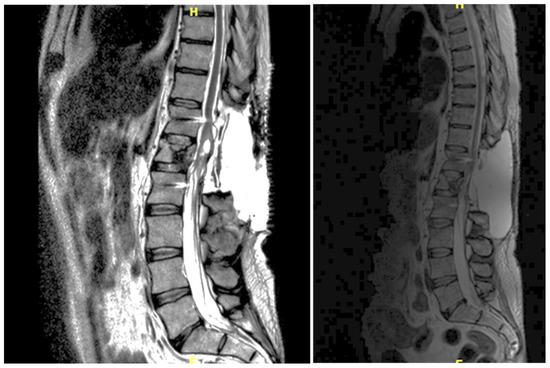

3.4.5. Case 5

| Level | T12–L2 | C5–C6 | T7–T10 | T8–T9 | T8–T11 |

| Location | Intramedullary | Intradural | Intradural–Extradural | Intramedullary | Intradural |

| Surgical treatment | lysis of adherences and syrinx cavity opening | resection of the cystic formation and adhesiolysis | resection of the cystic formation and adhesiolysis | resection of the cystic formation and adhesiolysis | resection of the cystic formation and adhesiolysis |

| Complications | CSF fistula | infection | None | CSF fistula | None |

| KPS pre-op (%) | 70 | 50 | 70 | 80 | 90 |

| KPS post-op (%) | 80 | 50 | 60 | 90 | 80 |

| ASIA score pre-op | C | B | B | C | D |

| ASIA score post-op | D | B | C | C | D |